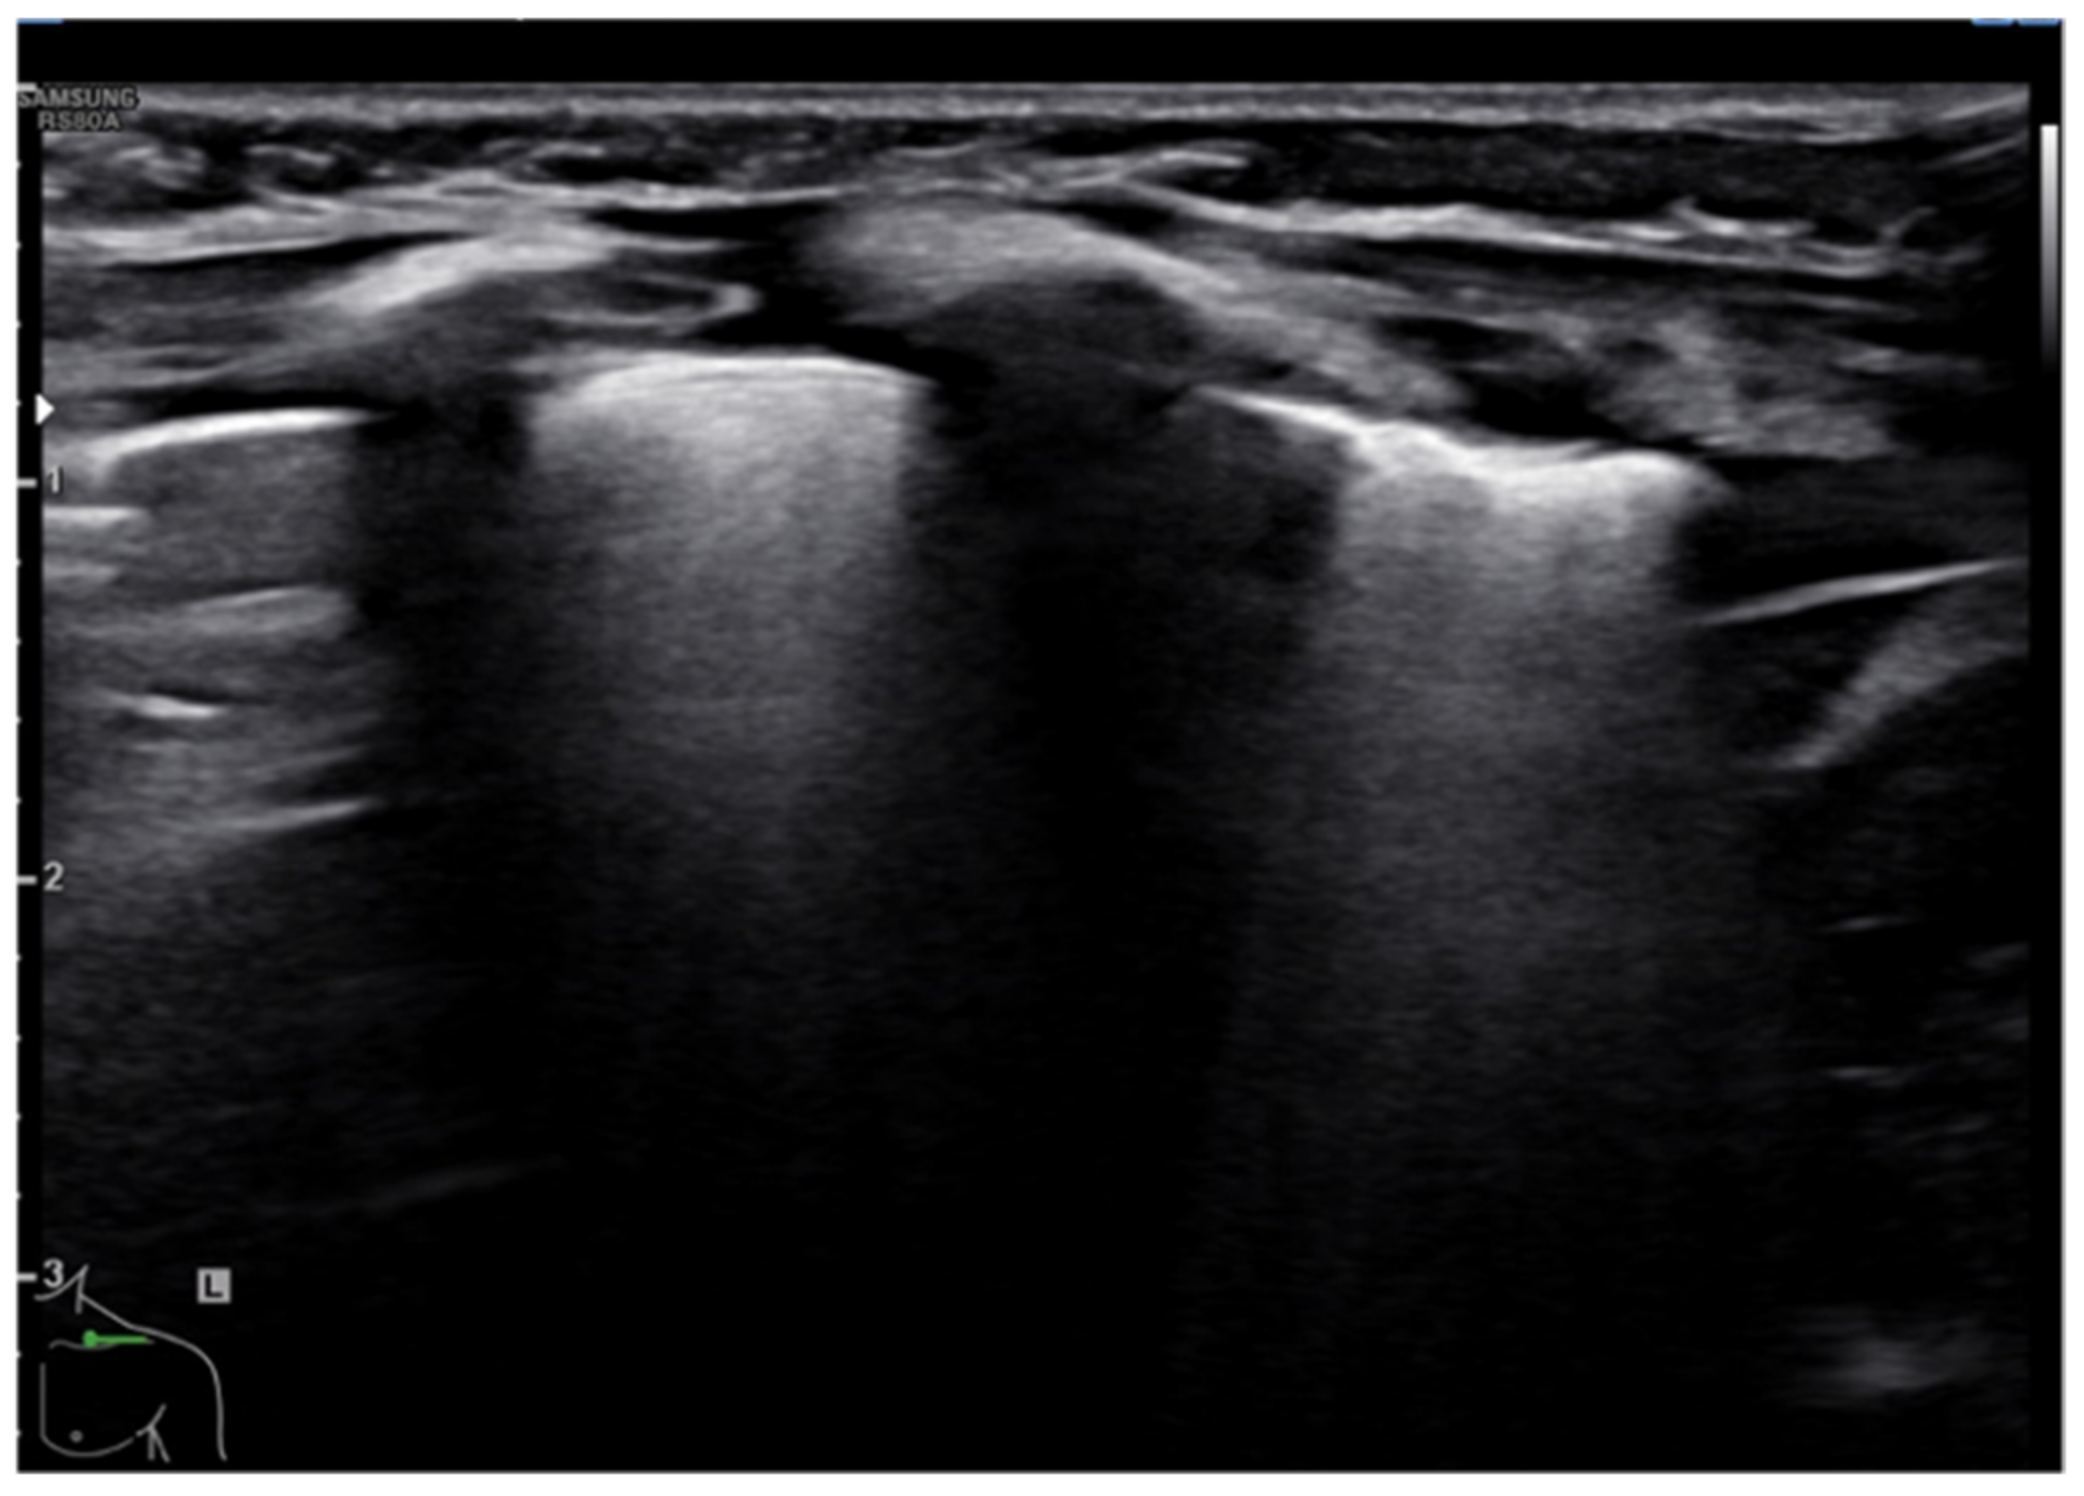

Pleural empyema refers to an infected, purulent and often loculated pleural effusion due to parenchymal infection that spreads to the pleural cavity. Ultrasound examination of the chest revealed a hypoechoic lesion with complex-septated effusions, passive atelectasis, width uniformity and smooth luminal and outer margins (Figure 12). Color Doppler can be used to differentiate the peripheral air-fluid abscess from empyema. In fact, color Doppler ultrasound vessel signals in pericavitary consolidation are a predictor of lung abscess [57,58,59,60].

Figure 12.

Hypoechogenic and highly corpuscular collection suggestive of pleural empyema (white arrow).